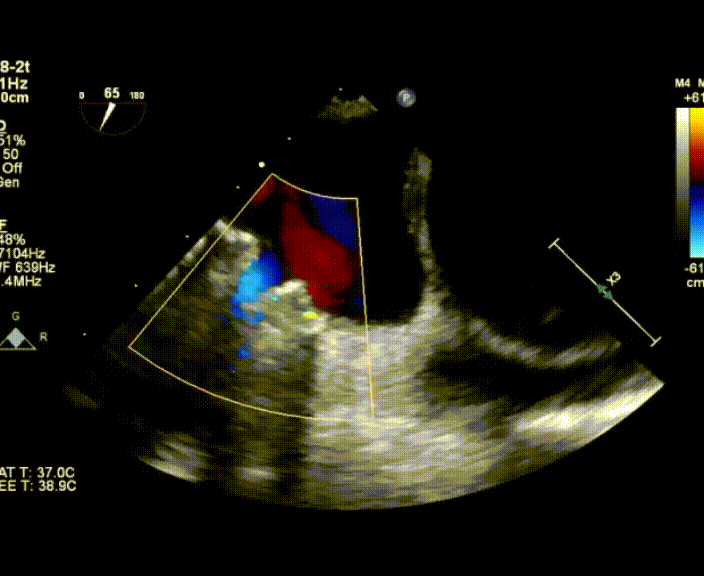

術中首先在局麻下穿刺股動脈、股靜脈,完成心導管檢查評估后轉為全麻,在食道超聲引導下穿刺房間隔,穿刺成功后將加硬導絲送入左上肺靜脈建立軌道,根據患者病情行球囊預擴張后植入6mm孔徑房間隔造孔支架,經透視及食道超聲評估支架左右盤展開良好,夾持于房間隔兩側,固定穩(wěn)定、位置良好,食道彩超顯示房水平右向左為主分流,分流孔直徑符合預期大小,心導管檢查評估達到預期效果,釋放造孔支架。術后12h患者下床活動,恢復順利,擬于近日完善術后評估后出院。

心房分流術是通過器械制造穩(wěn)定可控的心房間分流,適應證包括藥物治療效果不佳的左心衰或肺動脈高壓右心衰。本例患者為肺動脈高壓右心衰,術中成功放置MicroFlux®造孔支架在房間隔理想位置上,創(chuàng)造穩(wěn)定可控的心房間分流(此例患者以右向左分流為主),在不顯著增加左心負擔的情況下,有效降低患者右心房壓力、緩解體循環(huán)淤血,增加左心輸出量,改善患者癥狀、活動耐力和生存質量。同時,國內外也已經開展多項房間隔造孔支架在射血分數保留、射血分數中間值和射血分數降低的左心衰患者中的臨床研究,結果顯示對于經過充分的規(guī)范化藥物治療后仍控制不佳的患者,心房分流術可改善患者的癥狀及生存質量。